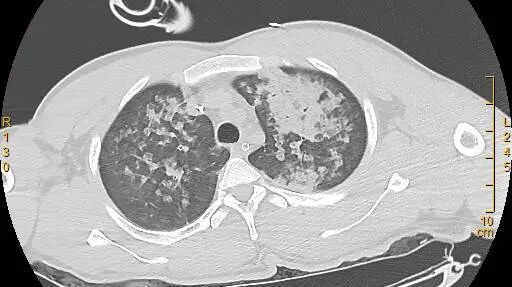

胸部 CT 如下:

图片